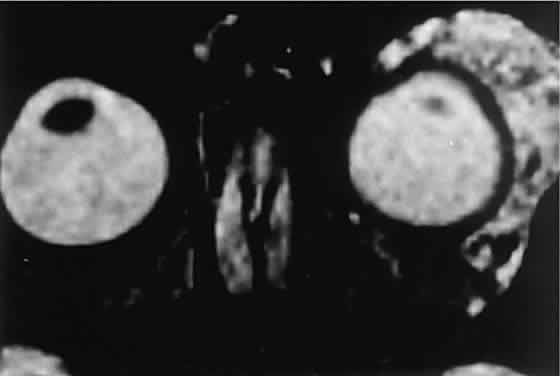

CT discloses a single or multilobulated mass, which represents only the blood cyst portion of the tumor (Fig. 14). Individual lobules may have different radiodensities depending on the presence of clots or liquefied blood within each cyst (Fig. 15). A generalized increase in orbital dimensions suggests a long-standing, probably congenital process. Echography may help differentiate the cystic components of lymphangioma from cellular rhabdomyosarcoma. Echography shows the blood cysts to be acoustically inactive spaces, with extremely low internal reflectivity (Fig. 16). Clots within the cysts can increase internal heterogeneity, however. MRI has virtually eliminated the need for diagnostic biopsy in this condition, because of its ability to show differing magnetic properties of suspended, degrading blood products (Fig. 17).

Fig. 14. CT appearance of hemorrhagic cysts in two different cases. A. A single intraconal cyst compressing the optic nerve. B. Multilobulated contiguous cysts. Intervening, nonexpanded segments are microscopic and not detectable with imaging studies.

Fig. 15. Lymphangioma with heterogeneous radiodensities. Clots were found in the denser anterior blood cysts, whereas the most posterior cyst had liquid contents.